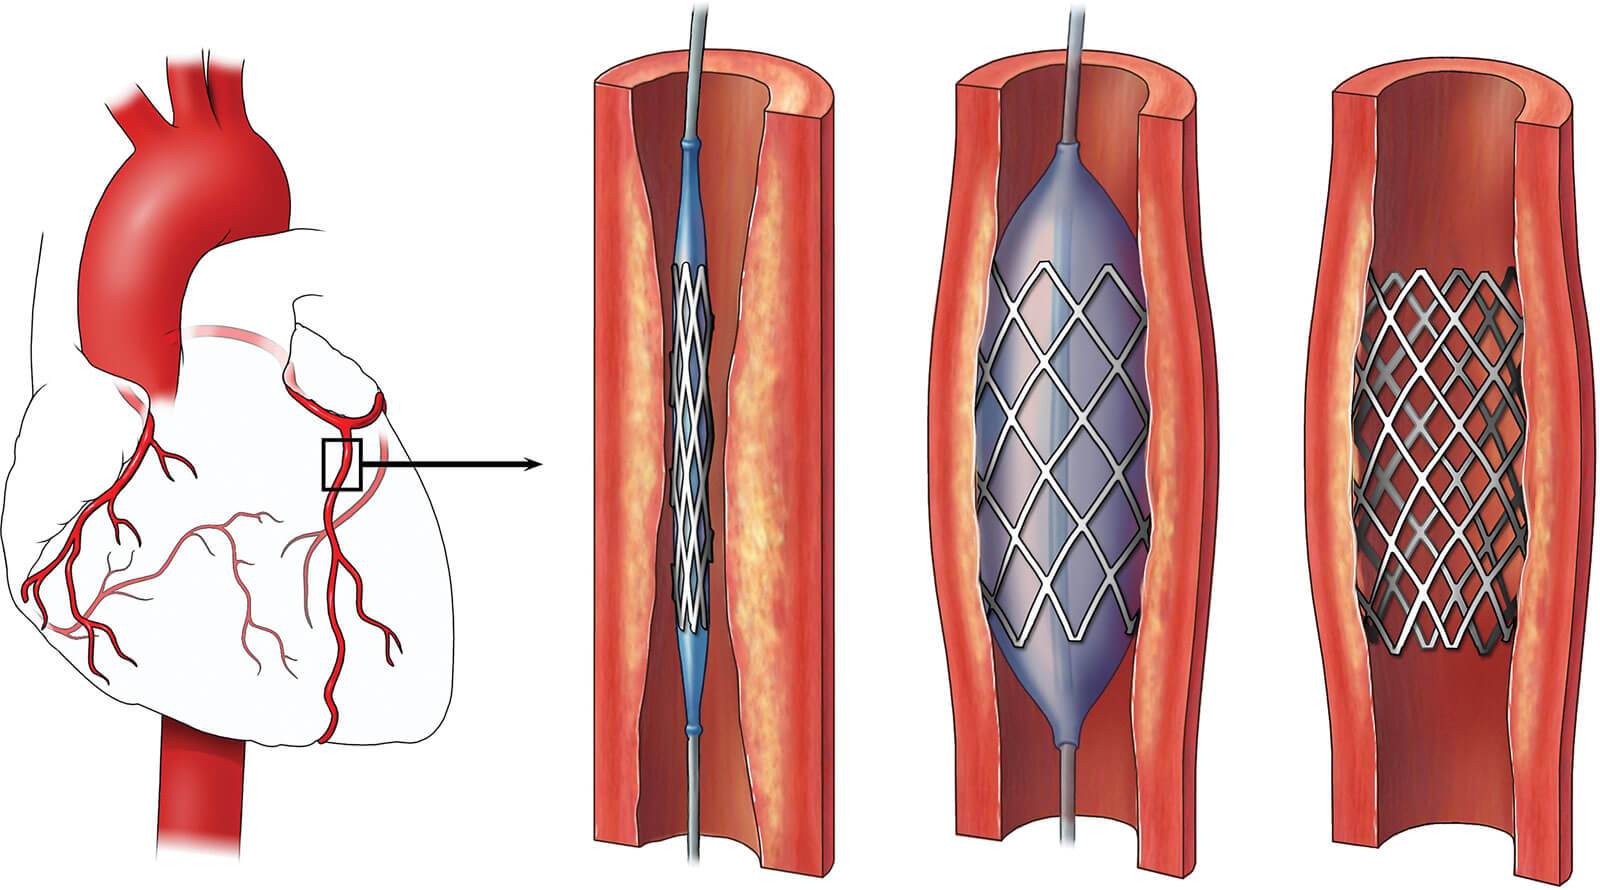

- для оценки проходимости шунтов и стентов коронарных артерий после операций стентирования и шунтирования;

Если КТ - коронарография выявит поражение коронарной артерии в виде ее сужения или полной закупорки ее просвета атеросклеротическими бляшками, то решается вопрос о необходимости выполнения стентирования (установка стена в сосуд) или коронарного шунтирования.

Если КТ - коронарография выявит поражение коронарной артерии в виде ее сужения или полной закупорки ее просвета атеросклеротическими бляшками, то решается вопрос о необходимости выполнения стентирования (установка стена в сосуд) или коронарного шунтирования.

В нашем госпитале выполняется операция стентирование коронарных артерий в рамках ОМС. Для госпитализации на операцию в Клинический госпиталь ИДК, необходимо получить направление определённого образца (форма №057/у-04) из поликлиники по месту жительства в АО «Медицинская компания ИДК» и записаться на операцию.